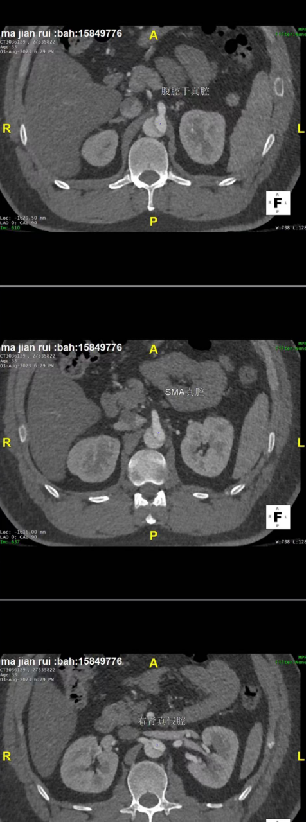

33岁肥胖患者(220斤),男性,合并重症鼾症,夹层破口位于主动脉弓小弯侧,假腔从降主至右髂外,多处破口,假腔体积大且累及右肾动脉,胸腔渗出多,呼吸功能差。

患者很年轻,不希望支架开窗或干扰左锁骨下动脉,但破口紧邻左锁骨下动脉小弯侧(小弯侧破口距锁骨下动脉只有7mm,大弯侧9mm),挑战比较大。需要评估是否延长近端锚定区以覆盖病变,同时避免影响重要分支血供。